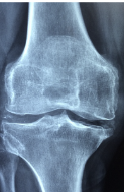

다리 관절에 좋은 음식 다리 관절에 좋은 운동 등 다리 관절 관련 정보 알아보도록 하겠습니다. 다리 관절은 우리 몸의 중요한 부분입니다. 다리 관절이 튼튼하고 유연하면 걷기, 뛰기, 앉기 등의 일상적인 활동을 쉽게 할 수 있습니다. 반면에 다리 관절이 약하거나 뻣뻣하면 통증이나 염증, 관절염 등의 질환에 쉽게 걸릴 수 있습니다. 그래서 다리 관절을 건강하게 유지하기 위해서는 적절한 운동이 필요합니다.

첫째, 골관절염입니다. 골관절염은 관절의 연골이 손상되어 관절에 염증이 생기는 질환입니다. 연골이 없어지면 뼈와 뼈가 마찰하게 되어 통증과 염증이 발생합니다. 골관절염은 나이가 들면서 자연스럽게 발생할 수 있으며, 비만, 외상, 유전 등이 위험 요인입니다.